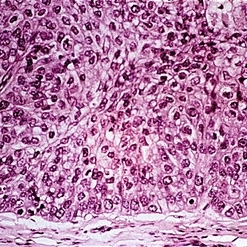

Slide 5-39 Slide 5-39Feb 25 2019 by Lancaster Course in Ophthalmology Lobule of with central foamy cells best seen in upper left. Condition/keywords: lobule